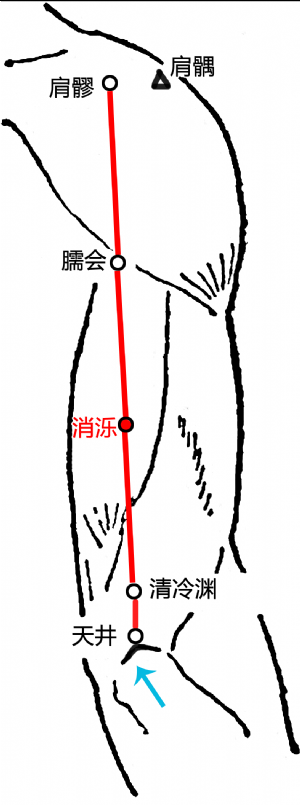

消濼爲經穴名[1](xiāoluò[2]TE12) 。出《鍼灸甲乙經》。屬手少陽三焦經[2]。消即消除,濼爲泊名,此穴如清涼之水,能清熱消渴,故名消濼[2]。消濼穴主要用於頭項疾患等:如寒熱,頭痛,齒痛,頭暈,頸項強急,肩背拘急,肩周炎,項強,臂痛,上肢麻痹,肩背痛,癲癇,偏頭痛,頸項痛,背部腫痛,頸椎病,頸項強痛,背腫等。

標準定位:消濼穴在臂外側,當清冷淵與臑會連線的中點處[4]。

消濼穴位於臂後區,肘尖(EX-UEl)與肩峯角連線上,肘尖上5寸[4]。

消濼穴位於肘尖(尺骨鷹嘴)與肩髎穴連線上,當清靈淵與臑會穴連線之中點處,前臂盡力旋前,在肱三頭肌外側頭隆起的下緣[5]。

消濼穴在上臂的位置

消濼穴在上臂的位置

正坐垂肩,前臂旋前,先取三角肌後下緣與肱骨交點處的臑會穴,當臑會與清冷淵之間的中點處是該穴。

消濼穴位於臂後區,肘尖(EX-UEl)與肩峯角連線上,肘尖上5寸[5]。